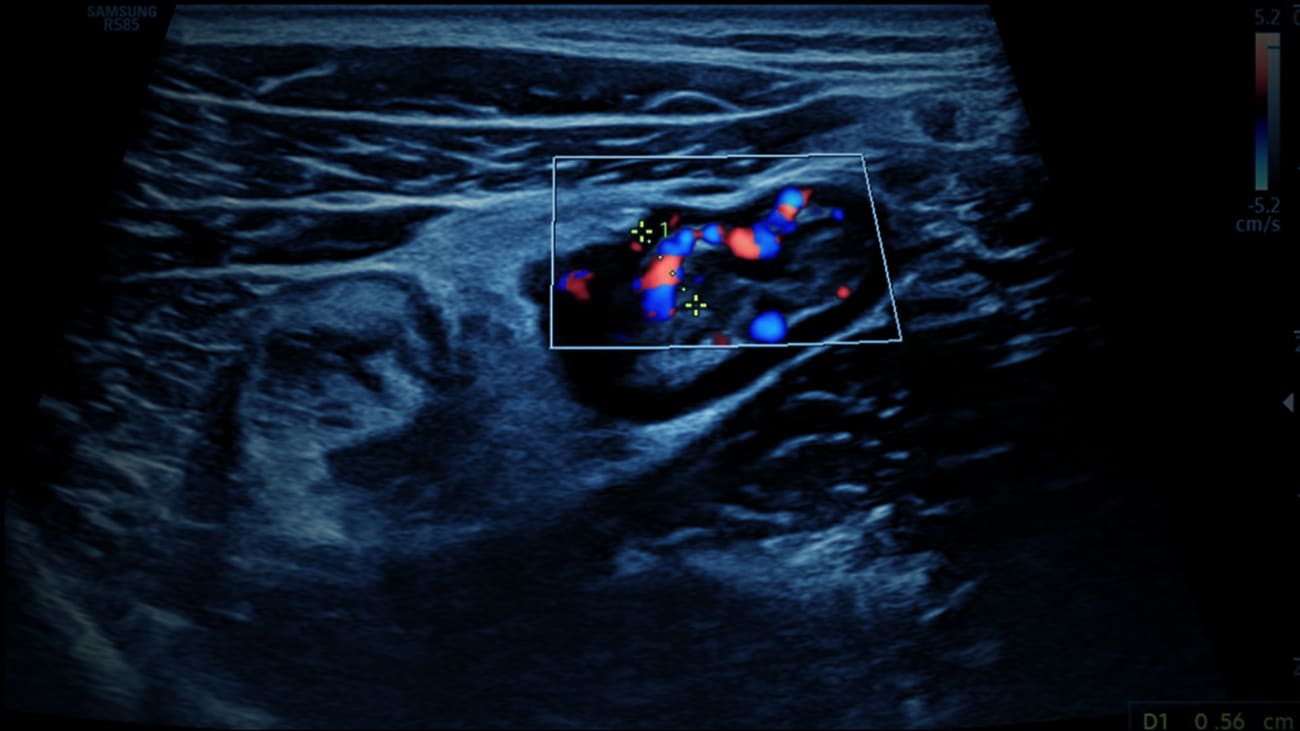

Bringing Ultrasound to the Bedside to Rapidly Diagnose and Treat IBD

The Susan and Leonard Feinstein Inflammatory Bowel Disease Clinical Center at Mount Sinai is the only center in the country that is currently using ultrasound to monitor inflammation in inflammatory bowel disease patients.